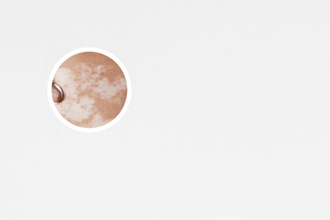

白斑的早期癥狀圖

白斑的早期癥狀較顯然的特征就是皮膚顏色的改變。在白斑部位,皮膚的色素會(huì)逐漸消失,形成白色或乳糜色斑塊。初期白斑一般較小,局部色素消失程度也相對(duì)較輕。

隨著白斑的形成,皮膚上會(huì)出現(xiàn)不均勻的顏色變化。白斑通常會(huì)呈現(xiàn)為白色或乳白色的斑塊,邊緣有時(shí)會(huì)出現(xiàn)清晰界限,有時(shí)則比較模糊。特別是在暴露于陽(yáng)光下時(shí),白斑的顏色差異可能更加顯然。